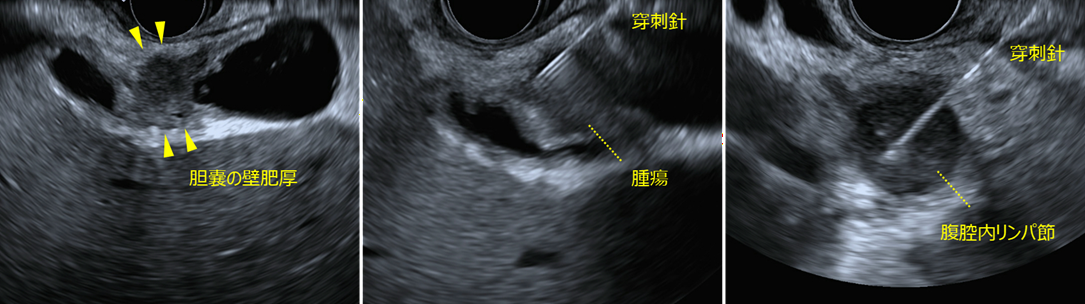

EUS所見

左:胆嚢壁肥厚を認めます。

中:十二指腸から胆嚢壁肥厚部を穿刺しました。

右:腹腔内の腫大したリンパ節を胃内より穿刺しました。

EUS-FNAで採取した組織の検査の結果、胆嚢病変およびリンパ節のいずれからも腺癌が確認されました。これにより、胆嚢癌およびリンパ節転移と診断されました。胆嚢癌と診断後、速やかに化学療法が開始されました。